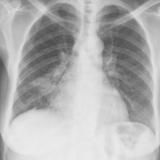

Case 2 PA

Date: 02/28/2004

Views: 3147